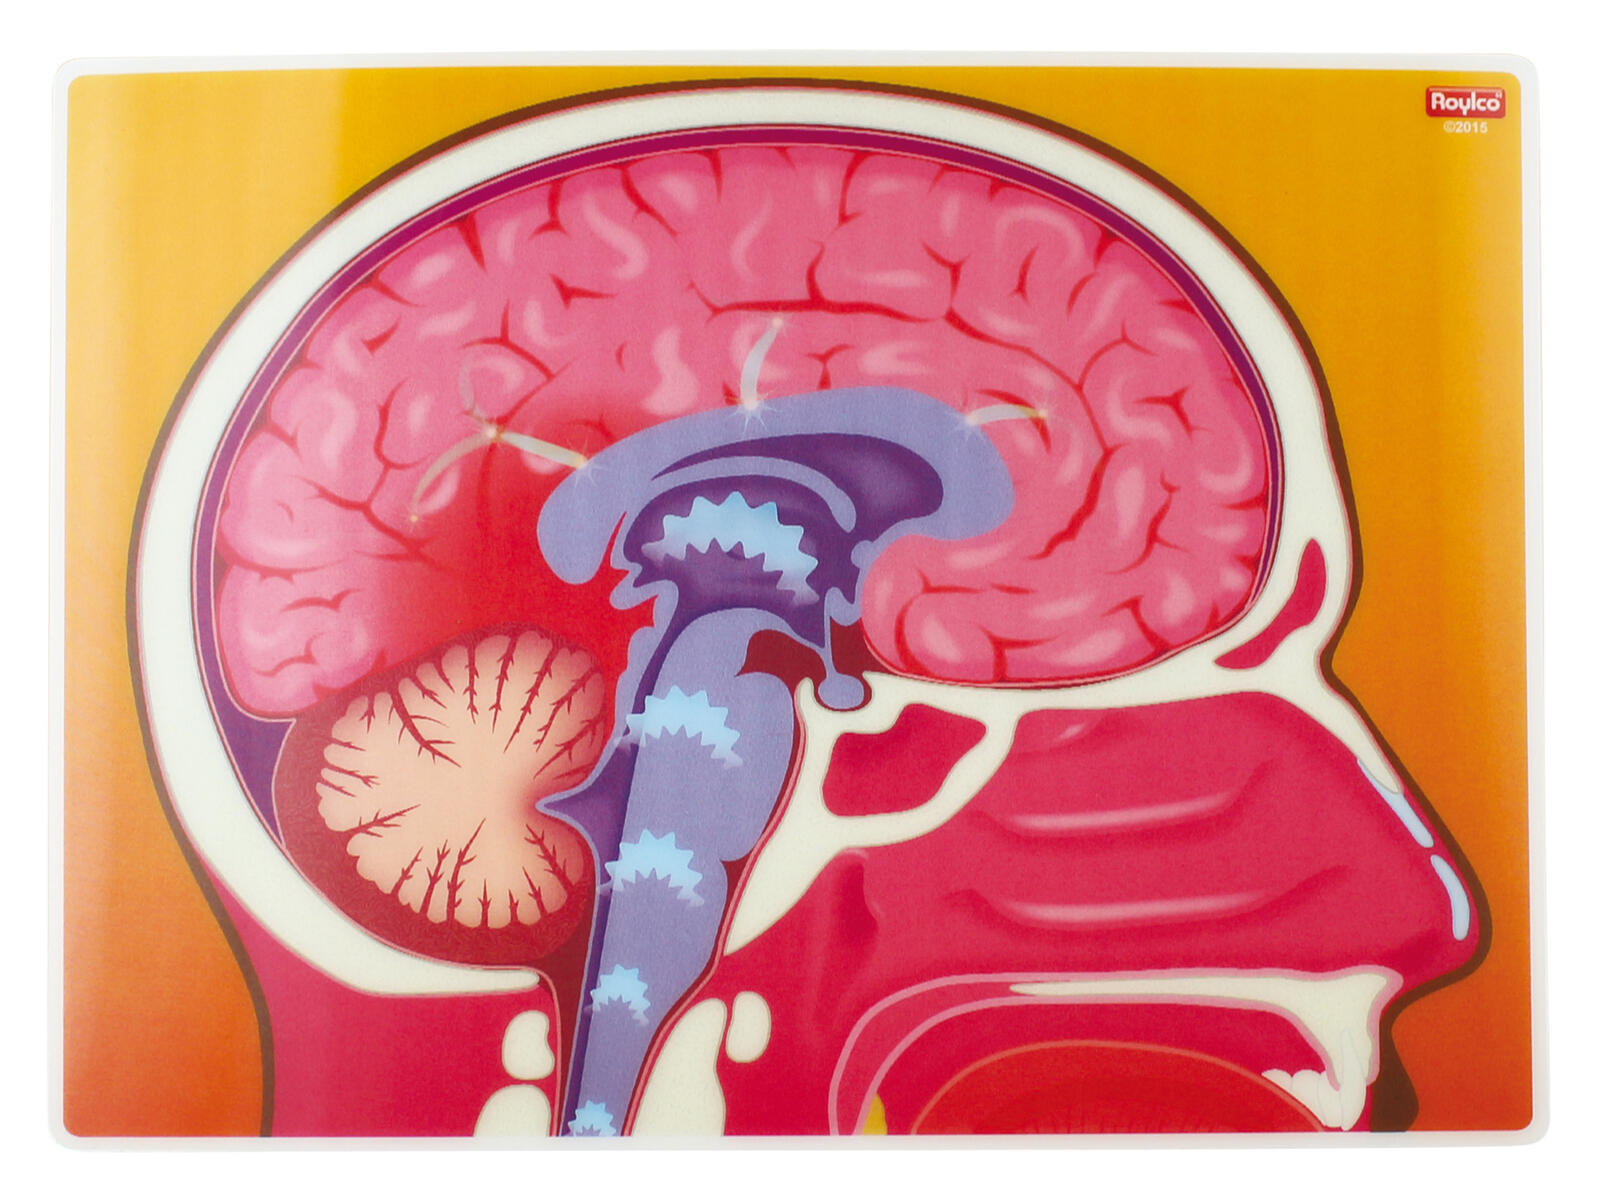

Innehåller 10 bilder som vid vinkling ändras och visar vad som händer i våra största organ i kroppen.

Innehåller bl.a. Hjärtat, Lungorna och hjärnan mm.